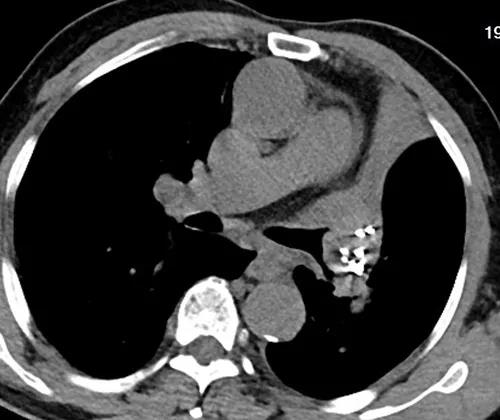

术后第二天胸部CT提示左肺门占位,左上肺不张,左肺门粒子植入术后

当复诊检查结果出来时,周大爷和江爱桂博士都显得异常激动,因为患者的支气管明显开通,左上肺复张,左肺实体病灶缩小50%。

术后联合化疗两月后复查胸部CT提示支气管明显开通,左上肺复张,左肺实体病灶缩小50%